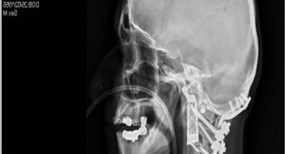

Dr. Ralph Mobbs, a neurosurgeon at the Prince of Wales Hospital in Sydney, called the procedure a “world first.” The surgery was performed on a patient with chordoma, a rare form of cancer that occurs in the bone of the skull and spine. As Wired UK reports, the 60-year-old patient was affected in the two vertebrae responsible for turning the head — meaning that, if the 15-hour surgery had failed, he would have been left paralyzed.

Because of the position and function of these vertebrae, however, they’re extremely hard to replace — they must be an exact fit. Mobbs decided to 3D print the replacements instead, and worked with Anatomics, an Australian medical device manufacturer, to design and build the implants, which were made from titanium. The company also printed exact anatomical models of the patient’s head for Mobbs to practice on before the surgery.